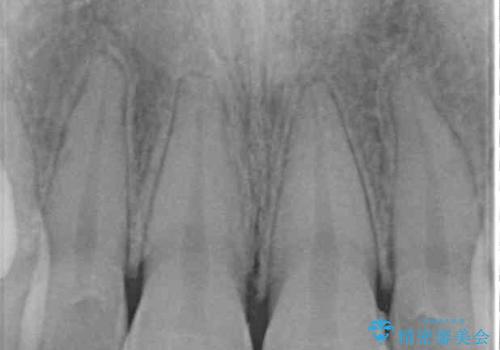

むし歯はなく、矯正治療で咬み合わせが改善していたので、侵襲量の少ないラミネートベニアにて治療することとしました。

ラミネートベニアは切削量が少ないことがメリットとしてあげられますが、色調を周辺と合わせられないこと、接着境界線が長く汚れや歯石が溜まりやすいことがデメリットとして考えられます。

また、接着境界線にむし歯がある場合には適用外となるなど、適用症例を選ぶため、治療に際して担当医としっかりと相談することが大切です。